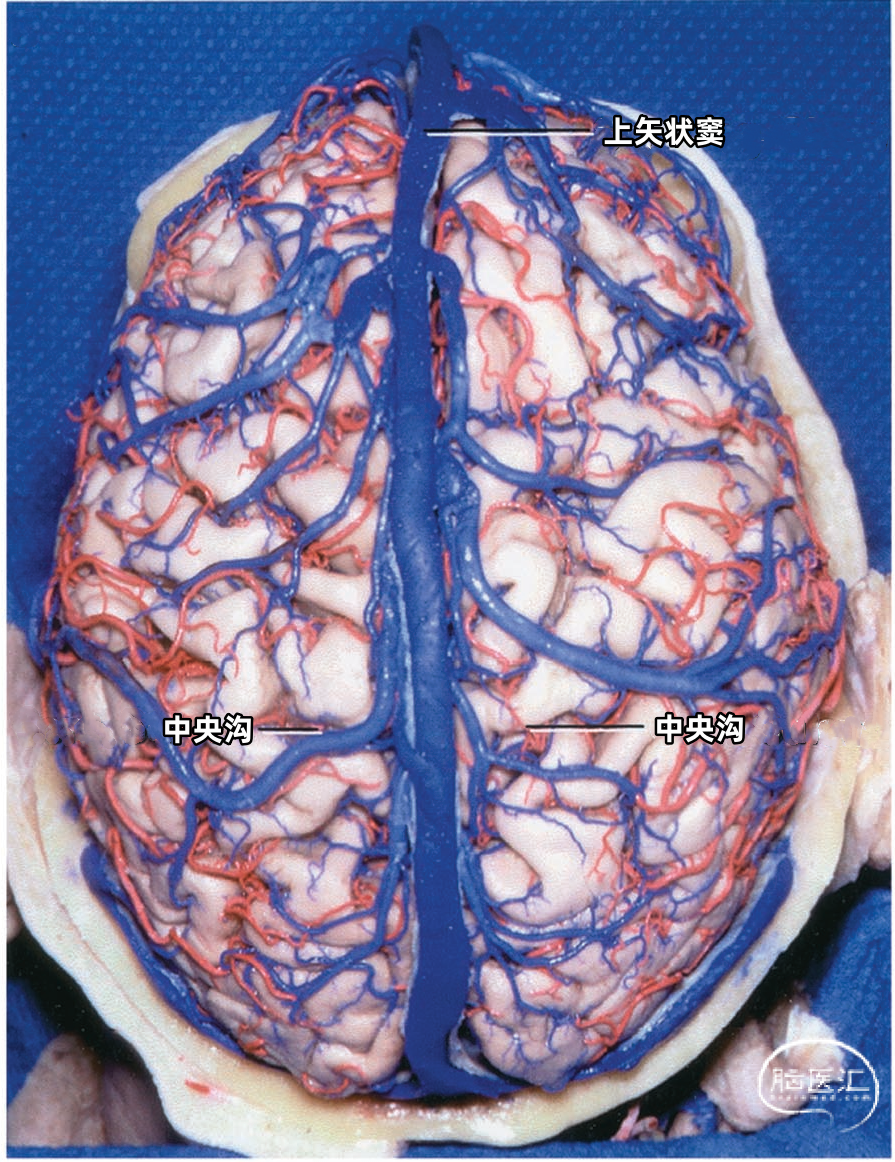

静脉腔隙(Venous lacunae),也称为静脉湖、静脉间腔、静脉间隙,来自硬脑膜的引流静脉在上矢状窦附近扩大形成静脉腔隙,它位于两层硬脑膜之间(下图)。 静脉腔隙主要接受硬脑膜内硬脑膜静脉的回流,也引流板障静脉的血液。 静脉腔隙内壁有蛛网膜颗粒(上图),进入上矢状窦的皮层静脉(上图)往往在静脉腔隙下方走行,直接汇入矢状窦,而不是直接进入静脉腔隙。大部分途经静脉腔隙下方的静脉与静脉腔隙分别开口入窦,但有些静脉与静脉腔隙有共同的入窦开口,极少数的静脉直接引流入静脉腔隙。 也有桥静脉(上图)先在窦旁潜行进入硬膜再汇入窦,硬膜内潜行使空腔扩大形成硬膜窦。静脉腔隙和硬膜窦都与矢状窦相通。 额叶后部和顶部的静脉腔隙最大和最恒定,枕部和额叶前部的静脉腔隙较小(上图)。 通常每侧都有2或3个这样的静脉腔隙,额部一个小静脉腔隙,顶部一个大的静脉腔隙,枕部一个大小介于前两者之间的静脉腔隙。 在年龄大的个体,这些腔隙趋向于融合,以致于每侧形成一个纵长的腔隙(下图)。 下图示切除大的静脉腔隙,显露下方进入上矢状窦的静脉。左侧中央静脉在中央沟上端注入上矢状窦。右侧中央静脉向前越过中央前回加入上矢状窦。

下图示切除静脉腔隙,显示上矢状窦右侧面。可见静脉在静脉腔隙下方进入上矢状窦。额内侧静脉、额外侧静脉以及顶内侧静脉、顶外侧静脉经常在入窦前汇合成共干,然后进入上矢状窦。

多数皮层静脉由单根起始,逐渐接受属支。相邻区域的皮层静脉可汇合成为一支桥静脉,穿出蛛网膜下腔,最后汇入硬膜窦。另外,引流半球内侧、外侧和底面的静脉,可能在交界区形成为一支桥静脉,最后汇入一个静脉窦。大脑内侧和外侧的上升静脉经常在半球上缘汇合,并进入上矢状窦;半球外侧下降的引流静脉和半球底面向外的引流静脉可在半球下缘汇合,进入颅底的硬膜窦。少数皮层静脉加入脑深部静脉系统。 相邻区域的血管间有互补关系,即某一静脉引流的区域增多,则相邻静脉的引流范围随之减少。在脑叶或面的主要引流静脉组之间也有类似的互补关系。

根据引流半球外侧面、内侧面或底面,皮层静脉分为三组。三个面的皮层静脉可依据其引流的脑叶和皮层区进一步细分。皮层静脉引流区域和方向如下: 额叶外侧面(蓝色)由额极静脉、额前静脉、额中静脉,额后静脉、中央前静脉、中央静脉、额外侧裂静脉引流。 顶叶外侧面(黄色)由中央静脉、中央后静脉、顶前静脉、顶后静脉、顶外侧裂静脉引流。 颞叶外侧面(绿色)由颞前静脉、颞中静脉、颞后静脉、颞外侧裂静脉引流。

▼1.额叶

▼2.顶叶

上矢状窦组(上图 深蓝色)由回流至上矢状窦的静脉组成,包括引流额叶、顶叶、枕叶内侧、外侧面上部皮层以及额叶眶面前部的静脉。 注入上矢状窦的大脑外侧面静脉包括额极静脉、额前静脉,额中静脉、额后静脉,中央前静脉、中央静脉、顶前静脉、顶后静脉、枕静脉和Trolard静脉。 注入上矢状窦的大脑内侧面静脉(上图 蓝色)包括额前内侧静脉,额中内侧静脉、额后内侧静脉、旁中央沟静脉、顶前内侧静脉、顶后内侧静脉和距状后静脉。 一般静脉在离开软膜-蛛网膜注入上矢状窦前,会在硬膜下腔有1~2cm长的游离段。这些静脉可能直接汇入上矢状窦,也可能先汇入硬膜内的硬膜窦,再进入上矢状窦。